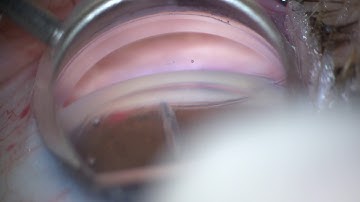

iTrack™ Procedural Steps: Viscodilation